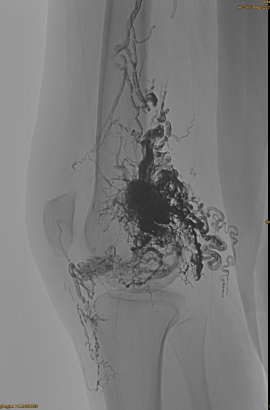

Grundläggande information om patienten: kvinnlig, 36 år; AVM bäcken, höft, knä, vänster OSG, flera pre - embolisering.

Produkter som används: 3st lava-34,14 st lava-18.

Initial DSA:

Slutresultat:

Knappast något venöst utflöde:

Sen fas, en annan embo nödvändig, men mycket bättre: